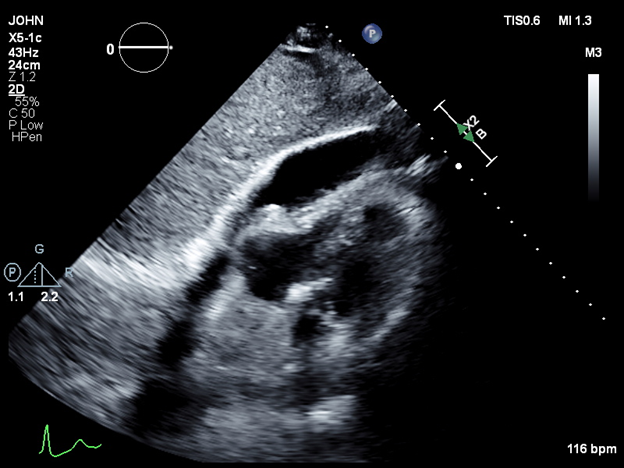

Case Presentation: We present the case of a 70-year-old male with a medical history of atrial fibrillation, hypertension, hyperlipidemia, and chronic obstructive pulmonary disease (COPD), admitted for elective radiofrequency ablation for atrial fibrillation. In the immediate postoperative period, the patient became hypotensive, with a blood pressure of 60/40 mmHg, and developed tachycardia, with a heart rate of 118 bpm. A bedside echocardiogram revealed a pericardial effusion with tamponade physiology. The patient was emergently transferred to the intensive care unit, where he was intubated and started on norepinephrine. An arterial line and central venous catheter were placed. Echocardiographic findings confirmed a large pericardial effusion, and a pericardial window was performed, draining 300 mL of bloody fluid. The patient also presented with bilateral pneumothoraces, and esophageal perforation was suspected due to the presence of mediastinal air. Bilateral thoracostomy tubes were inserted. However, subsequent endoscopy ruled out esophageal perforation. After clinical stabilization, the patient was successfully extubated and transferred to the internal medicine service. Both thoracostomy tubes were removed, and the patient was safely discharged home.